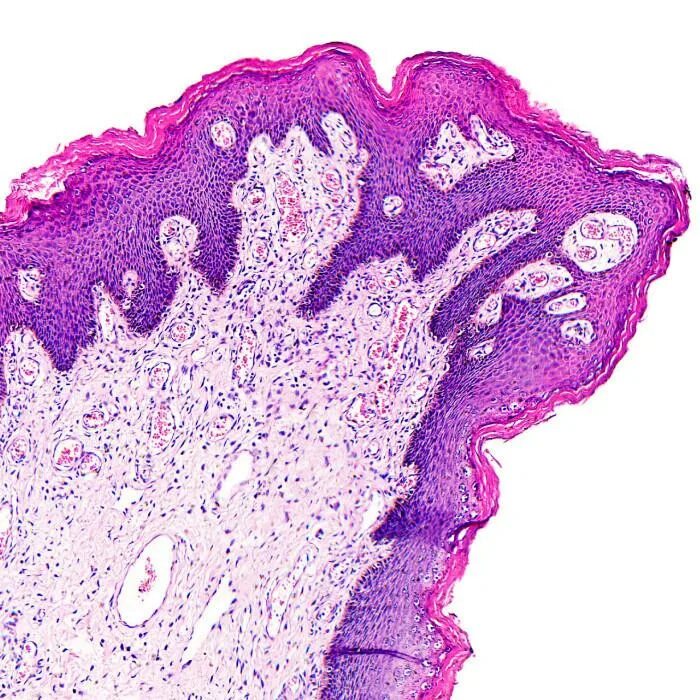

Папиллома гистология